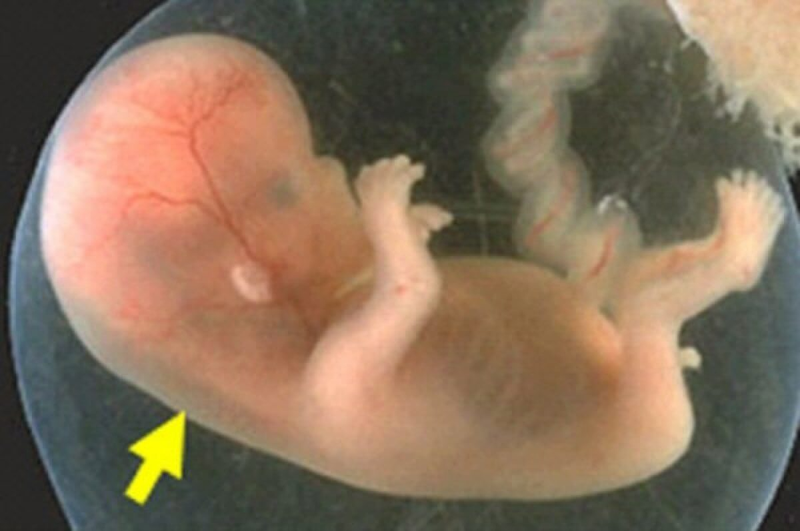

Khoảng sáng sau gáy, hay còn gọi là độ mờ da gáy, là một chỉ số được quan sát trong siêu âm thai, đo lường độ dày của lớp dịch nằm giữa vùng da sau cổ và xương cột sống của thai nhi. Thường xuất hiện từ tuần thai 11 đến 13 và biến mất sau tuần thai thứ 14, việc đánh giá độ mờ da gáy trong khoảng thời gian này có thể cung cấp những thông tin quan trọng về thai nhi.

Độ mờ da gáy được coi là một chỉ số quan trọng trong việc đánh giá nguy cơ mắc các bất thường nhiễm sắc thể ở thai nhi, bao gồm cả hội chứng Down và các dị tật bẩm sinh khác.